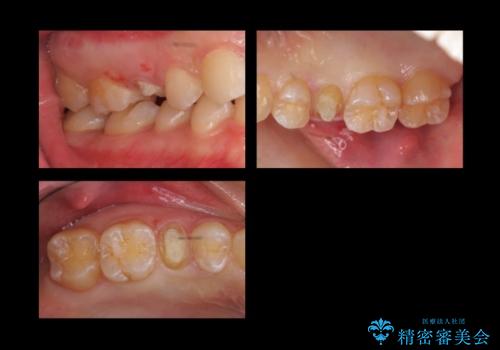

- 他院で治療途中、歯を被せたら頻繁に外れてしまうとのことでした。

診察すると、歯の高さがなく物理的に外れやすい状態となっていました。

歯周外科治療で歯の高さを出し、外れにくくしました。